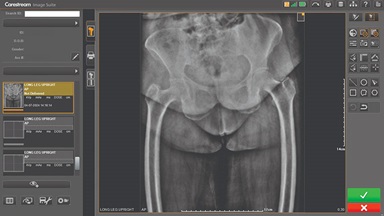

CARESTREAM Image Suite V4 MR11 has set a new standard for workflow efficiency, offering a robust set of features and functionalities to enhance clinical confidence in healthcare professionals. Using an auto-generated companion image from a single exposure, leverage a range of image processing options to increase diagnostic accuracy and enhance patient care.

More details

Download Sales Materials